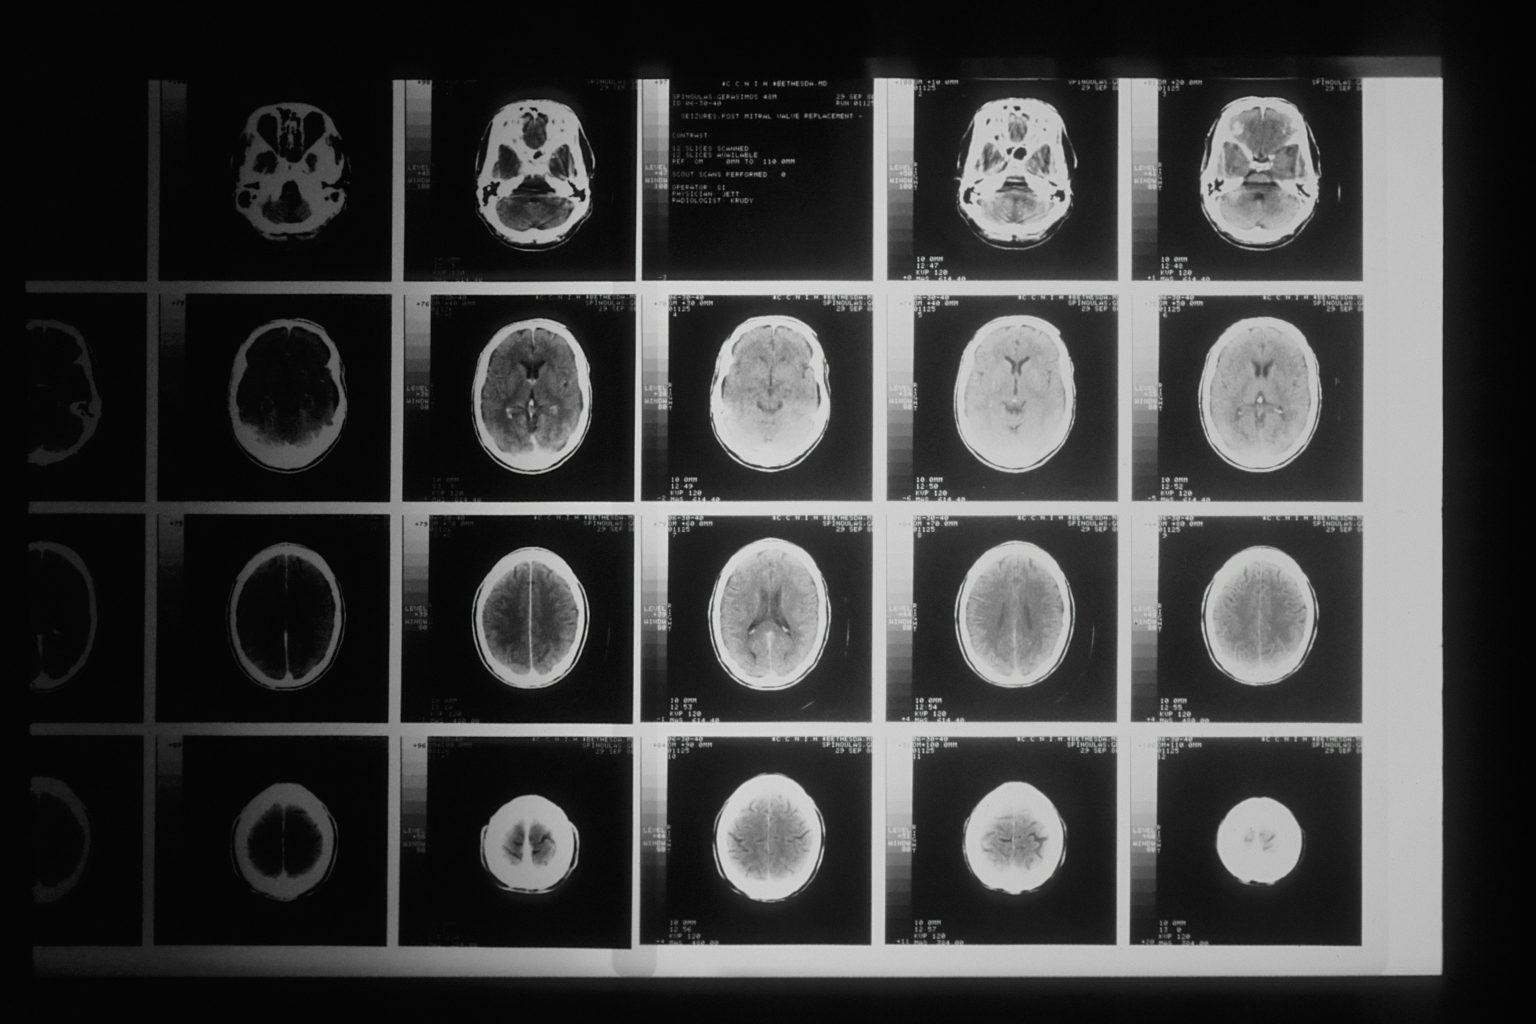

Alzheimer’s causes a gradual and irreversible loss of neurons. Early detection is crucial, yet current tests such as lumbar punctures or PET scans are invasive, expensive or difficult to access, and typically only detect the disease once it is already advanced.